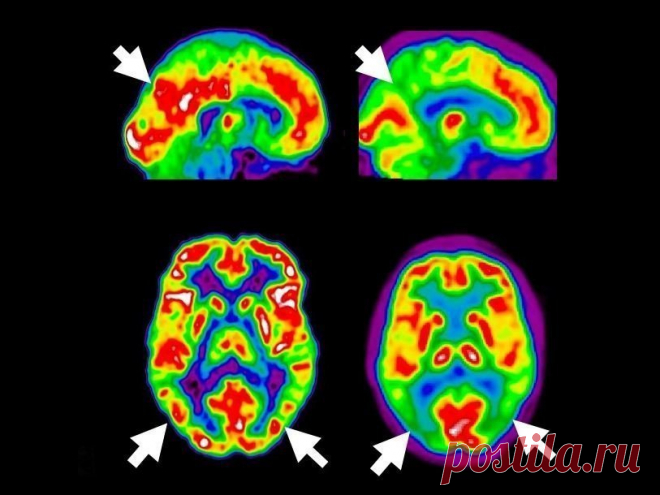

9 привычек, которые вам следует соблюдать, чтобы остановить деменцию и болезнь Альцгеймера, прежде чем она начнется! Очень эффективно! Что такое деменция? Деменция — это не болезнь, но на самом деле симптомы вызывают другие симптомы или травмы, которые воздействуют на